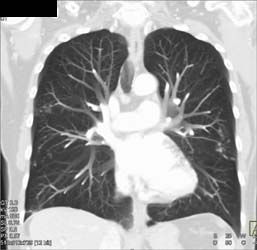

Sarcoma Chest Wall and Mediastinum